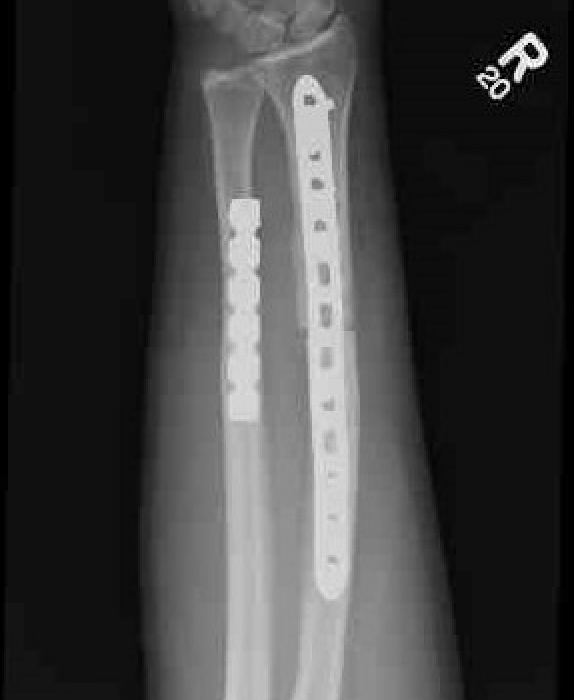

Galeazzi fracture

Galeazzi fracture with DRUJ disruption

Incidence of DRUJ instability after radius ORIF

Rettig et al J Hand Surg Am 2001

- 40 patients with Galeazzi fracture dislocations

- DRUJ instability after radius ORIF

- Type 1: radius fracture < 7.5 cm to articular surface: 55% DRUJ instability

- TYpe II: radius fracture > 7.5 cm to articular surface: 6% DRUJ instability

www.boneschool.com/galeazzi-fracture